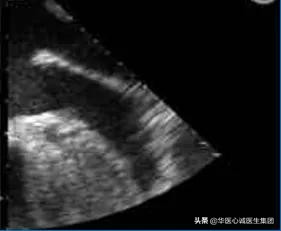

五、华法林嵴

对应于右心房的界嵴,是分隔左心耳和左上肺静脉的解剖结构。

食管超声断面图

牛角状的为患者的左心耳,上方为左上肺静脉。

二者间的隔膜为华法林嵴,类似棉签样改变。

超声心动图

可表现为Q尾征,见箭头处。

★★ 该结构是正常的,在临床诊疗过程中需要注意鉴别。

超声出现后,由于我们不认识该解剖结构,经常误诊为血栓之类的疾病,导致有些患者在早期时服用华法林(商品名Coumadin),因而得名。

上世纪80、90年代,日本学者曾提出“超声制造病”这一概念。指在没有超声检查之前,我们不知道某些疾病的存在。而在超声检查出现后,会把正常的结构误诊为疾病。界嵴和华法林嵴均属于超声制造病的典型代表,其实二者都是正常的解剖结构,但是被误诊为占位或血栓等。